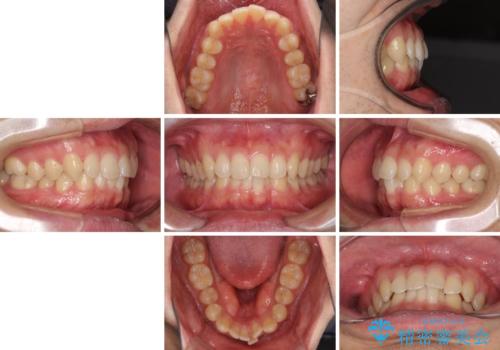

前歯の咬み合わせとデコボコを解消 インビザラインによる矯正治療

- 上下前歯のデコボコと深い咬み合わせを気にして来院された患者様です。

インビザラインによる上下歯列の拡大と、IPR(歯と歯の間を削る)にるスペースの獲得により、前歯のデコボコとディープバイトを改善することとしました。

もう少し下の前歯を整えたかったのですが、患者様の治療を早く終了させたいという希望により、細かい叢生を残しての終了となりました。